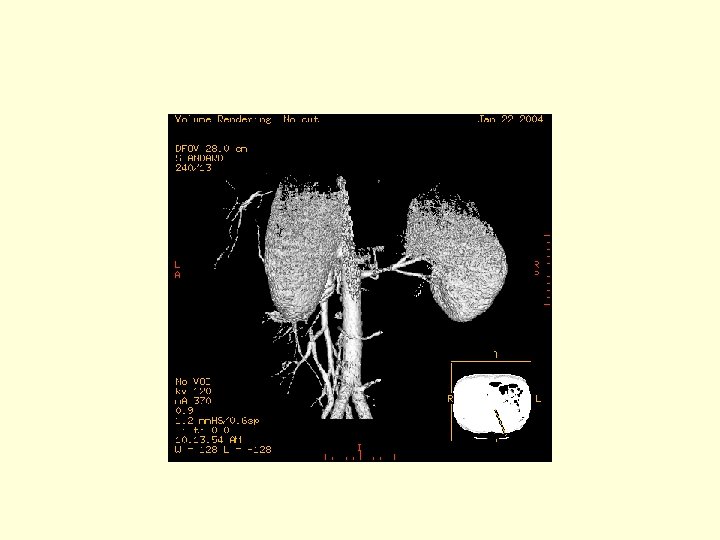

This is a 3 D image showing the branches of the SMA.

This is another 3 D image showing the vasculature of the SMA. Click through the next 20 frames to rotate the image.